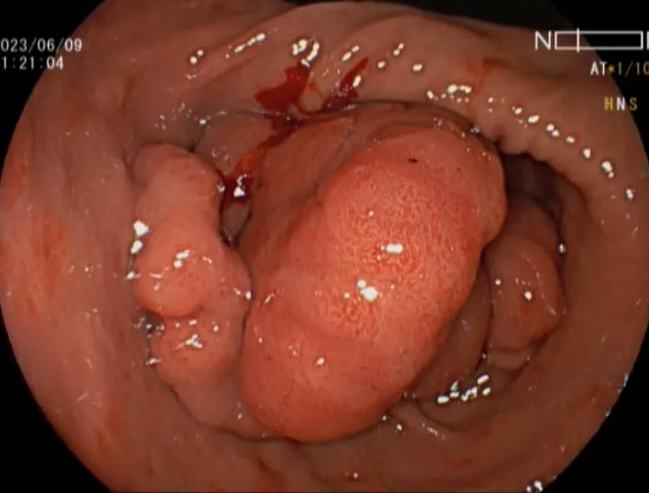

检查结果证实了大家的推测,患者胃镜提示:置底、体见弥漫性大小直径约0.5-2.0cm广基隆起,表面粗糙,边界清楚。胃窦见一大小约5x13cm隆起,呈分叶状.表面粘膜粗糙,边界尚清楚。肠镜见全结肠弥漫性大小约0.5-1.0cm 广基隆起。胃窦较大病变予取材送检,病检回报示:错构瘤性息肉。患者胃窦巨大病变,若不及时切除癌变风险极大,但患者年纪较轻,如果进行传统外科胃大部分切除术对患者后续生活质量影响较大。经讨论后,为患者进行胃镜下胃窦病变粘膜下剥离术为最佳手术方式,但是因患者病变巨大,手术难度大,剥离过程中出血及穿孔风险极大,这也为手术增加了不少难度。与此同时患者强烈要求就在本院进行手术治疗。

本着信任和解决难题的初衷,经过全科病历讨论后为患者制定了详细的手术方案及术前准备,历时六个小时,终于成功为患者完成了内镜下胃窦巨大肿物ESD 术,瘤体完整剥离,创面无残留,术中出血約50m1,离体标本大小5. 0X13CM。内镜诊断。术后病检符合P-J息肉诊断。